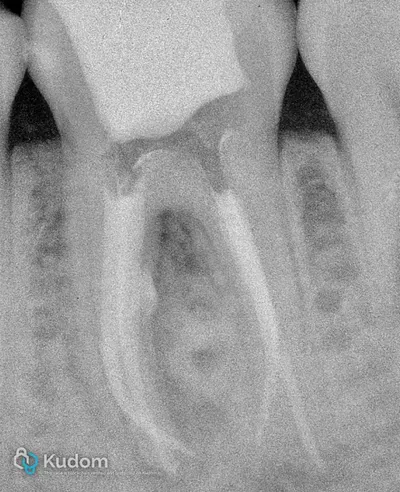

Ritrattamento endodontico complesso di un primo molare inferiore con lesione alla forcazione e otturazione di un canale laterale con successivo build-up per overlay a ricopertura cuspidale.

Ritrattamento di un molare inferiore con gestione di perforazione iatrogena a livello della forcazione, sotto l'imbocco radicolare.